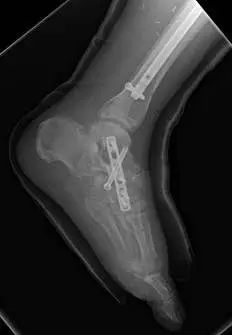

In the x-rays below there are fractures seen in the midtarsal bones that can occur with a high impact twisting injury where the foot is caught in something like the stirrup of a horse saddle or from direct high impact traums to the middle of the foot. The fractures can be seen from a view at the top of the foot (left) and side of the foot (right). This injury requires open reduction with internal fixation in order to re-align the fractured bones and prevent disability (Bottom left).

These are pics of the plate and screws stabilizing the fractures after ex fix was removed. An IM rod was also placed for a tibia fracture.